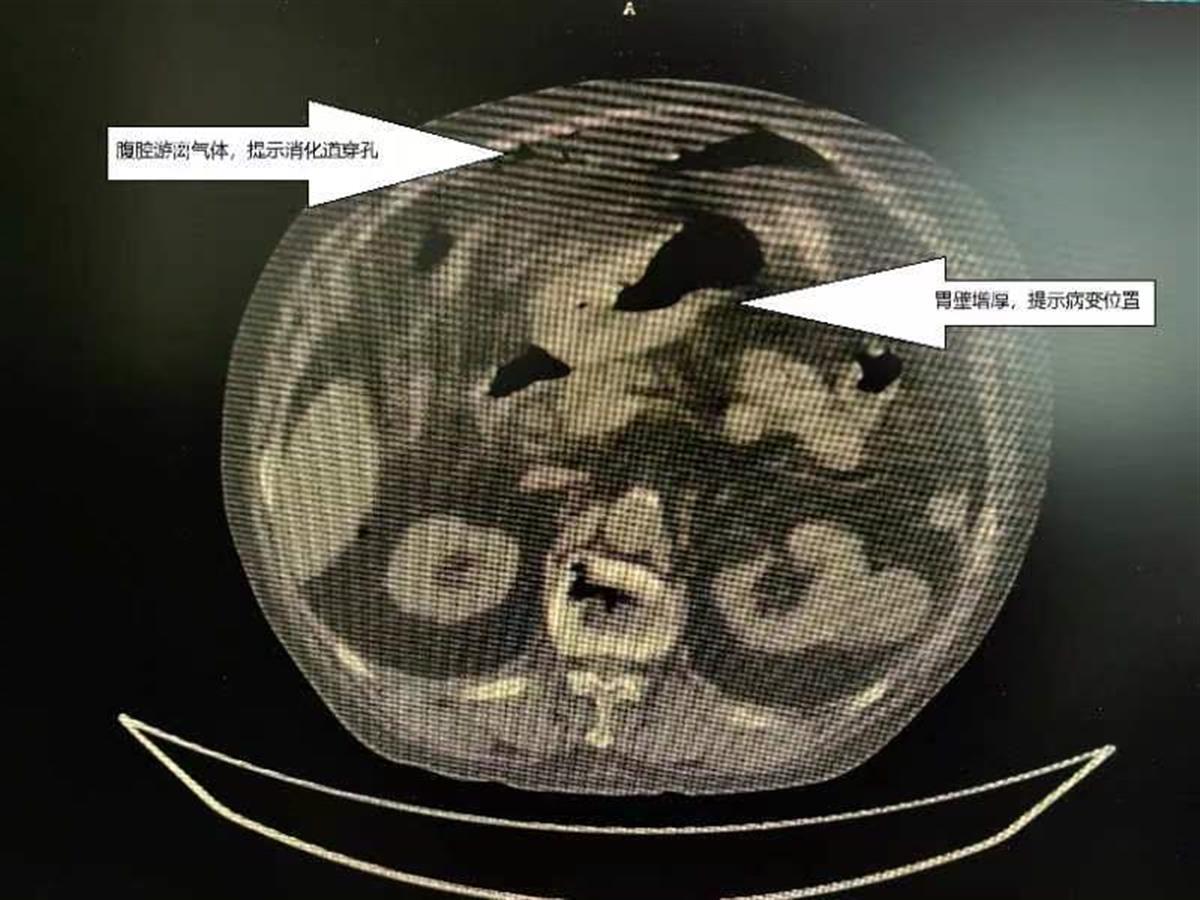

影像学检查发现刘爷爷有胃穿孔,和服用过量含糖皮质激素药物有关(通讯员供图)

在武汉市第四医院胃肠外科,医生接诊后发现刘爷爷精神萎靡,已经出现感染性休克。医生迅速为其缓解休克并完善相关检查。根据刘爷爷的症状及检查结果,医生判断刘爷爷有胃溃疡并出现穿孔,还查出了他患有高血压、糖尿病等疾病。术中,医生看到刘爷爷胃部有一个近3x4厘米的溃疡,其中有1厘米的穿孔。目前经过胃穿孔修补手术,刘爷爷情况好转,目前正在恢复中。